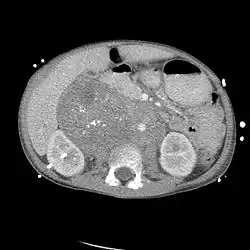

Die Diagnose erfolgt in den Frühstadien meist zufällig mittels Ultraschall, Computertomografie (CT) oder Magnetresonanztomografie (MRT), die aus anderen Anlässen angefertigt wurden. In der Folge führt die MIBG-Szintigraphie zur Lokalisierung des Primärtumors und der eventuell schon vorhandenen Metastasen. Die Skelett-Szintigraphie mittels Technetium-Phosphonaten wird zur Unterscheidung zwischen Knochenmarks- und Knochenmetastasen herangezogen. Die histologische Abgrenzung von Neuroblastomen zu anderen Tumorgruppen sowie die Einschätzung ihrer biologischen Dignität erfolgen üblicherweise auf Grundlage der international anerkannten International Neuroblastoma Pathology Classification (INPC). Ergänzend zur morphologischen Klassifikation hat sich die genetische Analyse des Tumorgewebes als ein wertvolles Instrument zur präziseren Einschätzung der Aggressivität des Tumors (Dignität) etabliert. Auf Basis einer großen Zahl molekulargenetisch gut charakterisierter Neuroblastome konnte in internationalen Studien eine differenziertere Risikostratifizierung entwickelt werden, die genetische Merkmale der Tumorzellen berücksichtigt. Die Kombination aus klinischen Daten, bildgebenden Verfahren, morphologischen Befunden und genetischen Profilen bildet die Grundlage für ein personalisiertes therapeutisches Vorgehen, wie es unter anderem im Rahmen der International Neuroblastoma Risk Group (INRG) und der INRG-Biologie-Initiative publiziert wurde.[1][2]